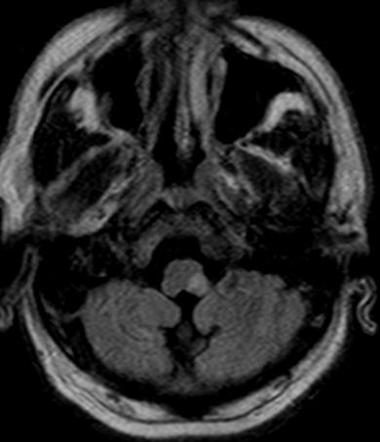

In this MRI image of the brain there is a region which has sufferd from and acute infarction/stroke. Can you recognize the region? if you can can , which are the structures (nuclei, pathways) that are most likely affected by the lesion and what could be the possible neurological outcomes in this patient ?

View this question